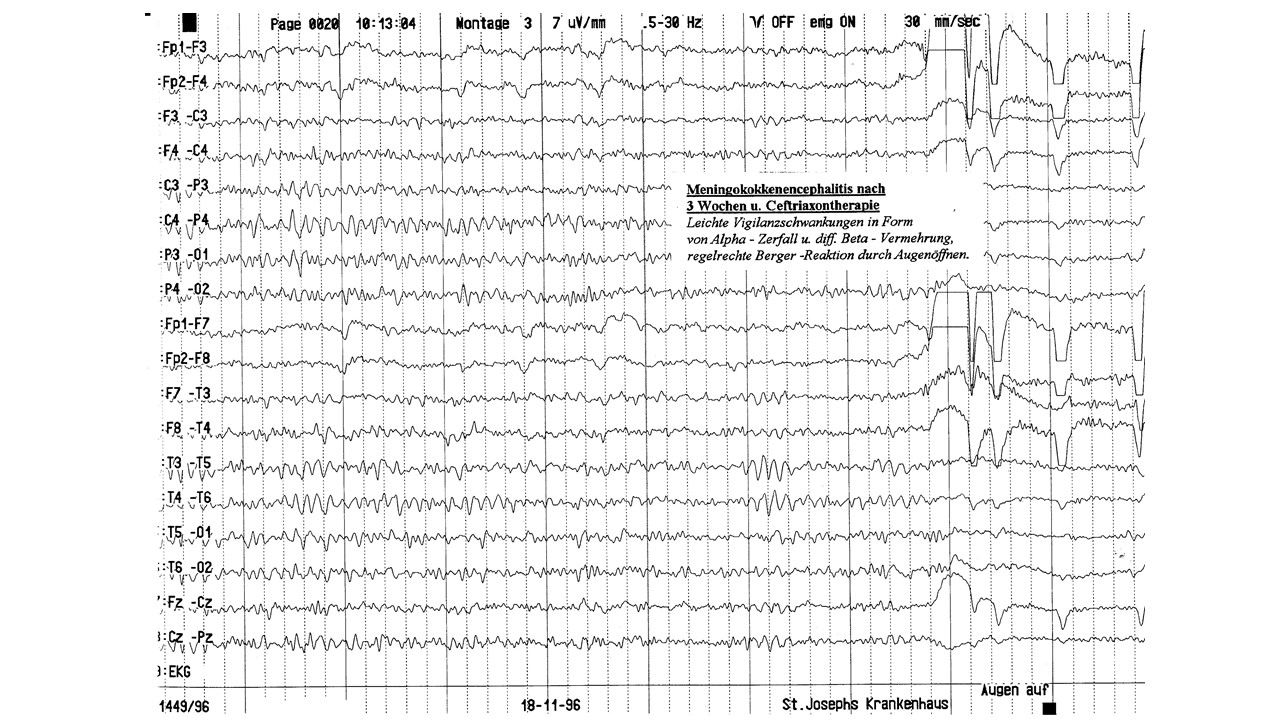

folie159.jpg